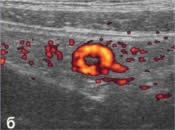

Иллюстрации: Флегмонозный аппендицит

у ребенка 11 лет.

б, д - продольное и поперечное сканирование

(соответственно) визуализируемого фрагмента червеобразного

отростка в режиме дуплексного допплеровского сканирования.

Прослеживается сосудистый рисунок в стенке отростка. |